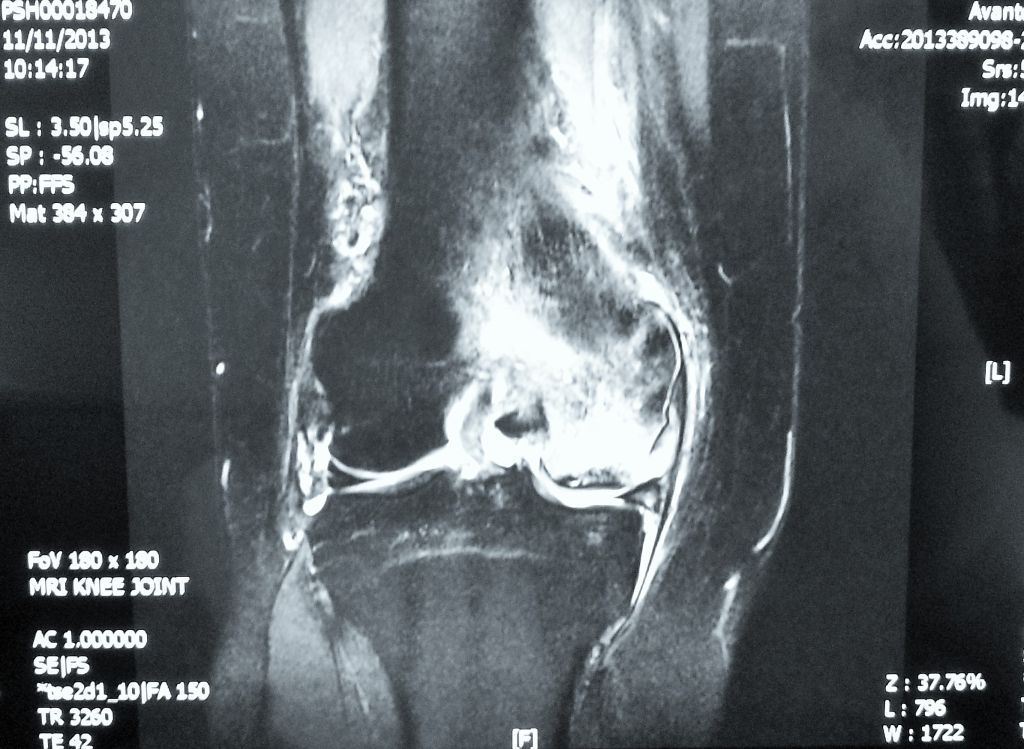

How Does the X-ray Look Like?

If the x-rays look normal but the pain is severe, always consider a diagnosis of AVN knee.

An MRI scan of the affected knee will be most useful.

In later stages, x rays may show bone damage and collapse.